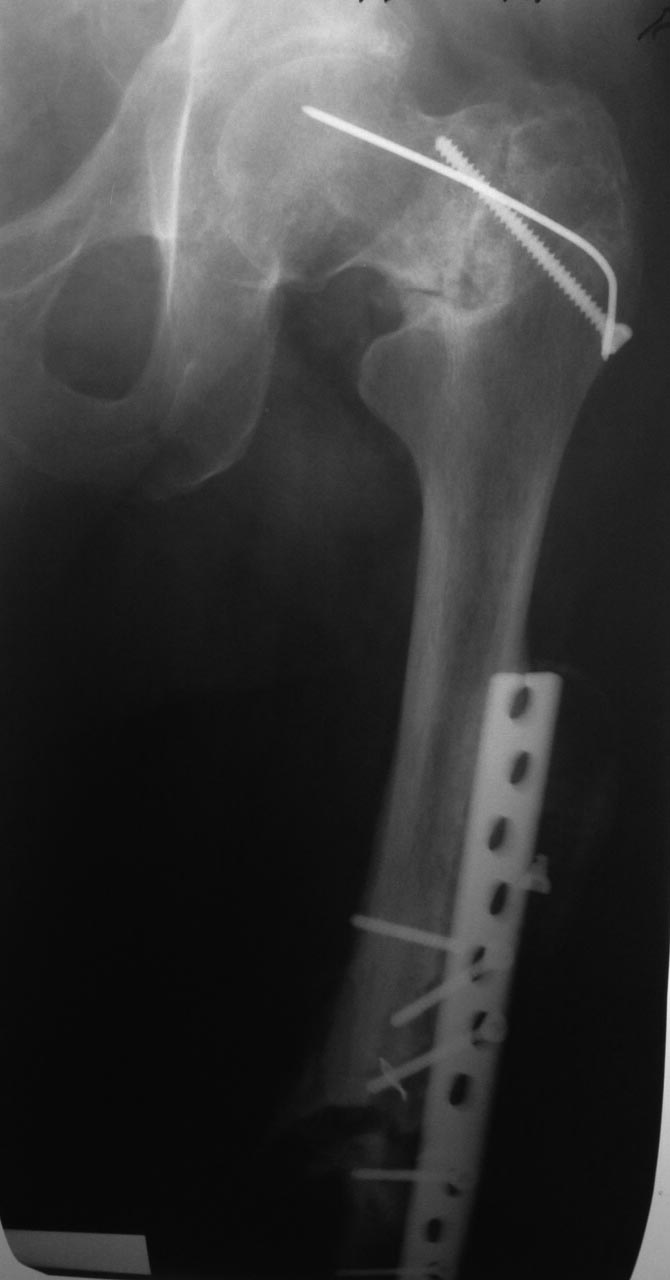

Уважаемые коллеги,помогите определиться с тактикой лечения.В отделение

поступил пациент с Ложным суставом левой бедренной кости.Сращение в

вертельной зоне также вызывает сомнение.

Пациент 1960 г.р.,оперирован в одной из клиник республики в 2012 году по

поводу сегментарного перелома бедренной кости.В настоящее время имеется

укорочение 3 см,патологическая подвижность и боли в области диафиза.

Пациент передвигается при помощи костылей с незначительной нагрузкой.

Планируется выполнить :

1)Удаление металлоконструкции,резекцию ложного сустава,остеотомия в

вертельной области,остеосинтез удлиненным стержнем PFN;

2) эндопротезирование тазобедренного сустава, резекция ложного сустава,

ретроградный биос. Интересно узнать что бы вы сделали в

такой ситуации.